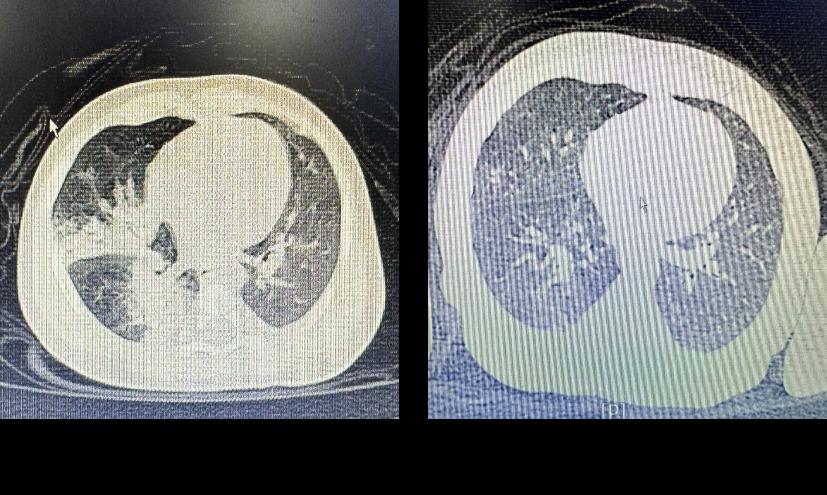

近期,我院小儿内科收治了一名仅58天的重症肺炎患儿,入院时患儿精神萎靡,高热不退,三凹征阳性,胸部CT右肺中叶及下治疗前治疗后叶均有实变。患儿年龄小,病情危重,入院后虽然给予抗感染治疗但症状无缓解,只有尽快解决患儿的肺实变,病情才会出现逆转。在制定了新的治疗方案后,王慧渊主治医师为患儿进行了支气管肺泡灌洗治疗。灌洗后,患儿的体温迅速下降,呼吸困难缓解,精神也明显好转。经过儿科医护的全力就治,患儿治愈出院。